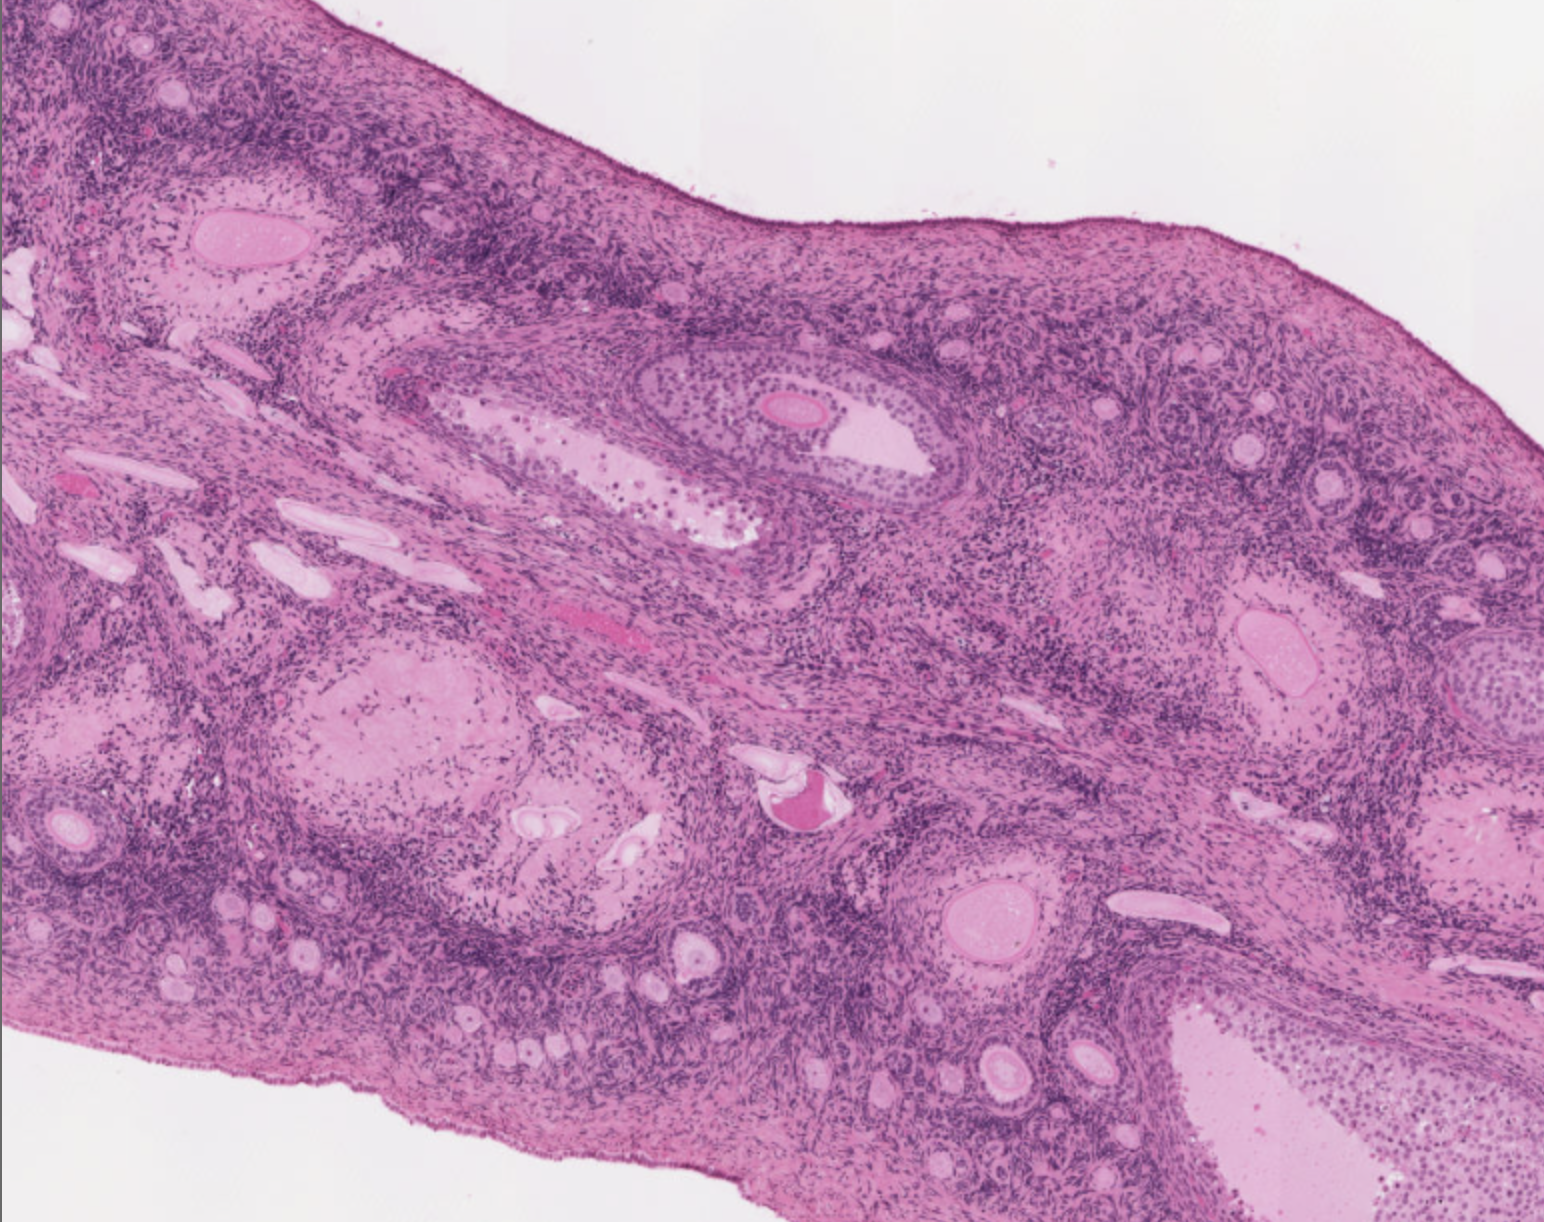

How can you identify the thyroid gland on a slide?

Identify follicles, colloid, and follicular cells (?)

What is the thyroid gland composed of?

Follicles: round structures where thyroid hormones are synthesized and released

What substance are found in the follicles? What is it rich in?

Colloid; iodine